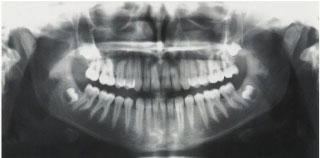

歯を支えている骨の状態や目で見えない部分を調べます

初期治療I お口の中の現状を詳しく知るため10枚のX線写真撮影・デジタルカメラを使用してお口の中のカラー写真数枚撮影・歯周ポケットの深さを測る検査・唾液の量、質 の検査を行い患者様の口腔内の必要な治療についてご説明します。